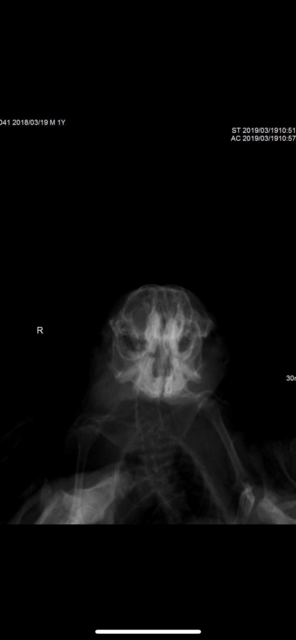

Приговор Малокклюзия генетическая.

После проведённых анализов, нарушений сбоя работы организма не нашли.

Вывод один-генетическая наследственная патология.

К сожалению Юкатана пришлось усыпить.

Корень зуба пророс в носовой пазух, животному было тяжело дышать, и оно испытывало боли.

Ямато пока поживёт на обезболивающих, у него чуть «лучше» обстоят дела , но это временно к сожалению.

Около месяца назад мне поступила информация от Фроловой о том, что у одного из ее мальчиков, рожденного в моем питомнике, Юкатана, диагностировали неоперабельную малокклюзию и его планируют усыплять.

Я стала более тщательно наблюдать за родителями мальчика. И у папы Чизкейка обнаружила неравномерно сточенные резцы. Поскольку зверю проблема дискомфорта не доставляла, а в разведении он не участвовал уже год и участие его пока не планировалось, я решила посетить врача в ближайшее свободное время. Но, в связи с последними бурными обсуждениями данного вопроса и с тем, что по словам Фроловой, подобное заболевание возникло и у Ямато, еще одного сына Чизкейка от другой матери, я перенесла наш визит к врачу, и мы были там сегодня.

Чизкейку (http://degu.by/site/genbasa/?id=34 ) поставлен диагноз: Малокклюзия, дентальная болезнь, стоматит.

Мальчик официально выведен из разведения на основании поставленного диагноза.

По его мнению генетические проблемы в области стоматологии проявляются в первые месяцы после рождения, иногда чуть позже, но всегда до достижения дегу возраста 1 год.

У Чизкейка озвучена именно такая причина. Воспаление десны (возможно стоматит), зверь перестал пользоваться одной стороной при жевании и это отразилось на состоянии резцов. Корни также отросшие.

Корни не прорастают сами по себе. Для этого должна быть проблема внутри рта. Зверь жует меньше обычного из-за болевых ощущений, зубы не стачиваются, становятся длиннее нормы и при жевании зубы давят друг на друга, из-за этого происходит продавливание корней вглубь.